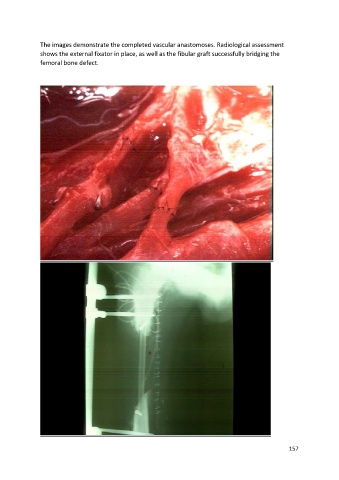

The images demonstrate the completed vascular anastomoses. Radiological assessment

shows the external fixator in place, as well as the fibular graft successfully bridging the

femoral bone defect.